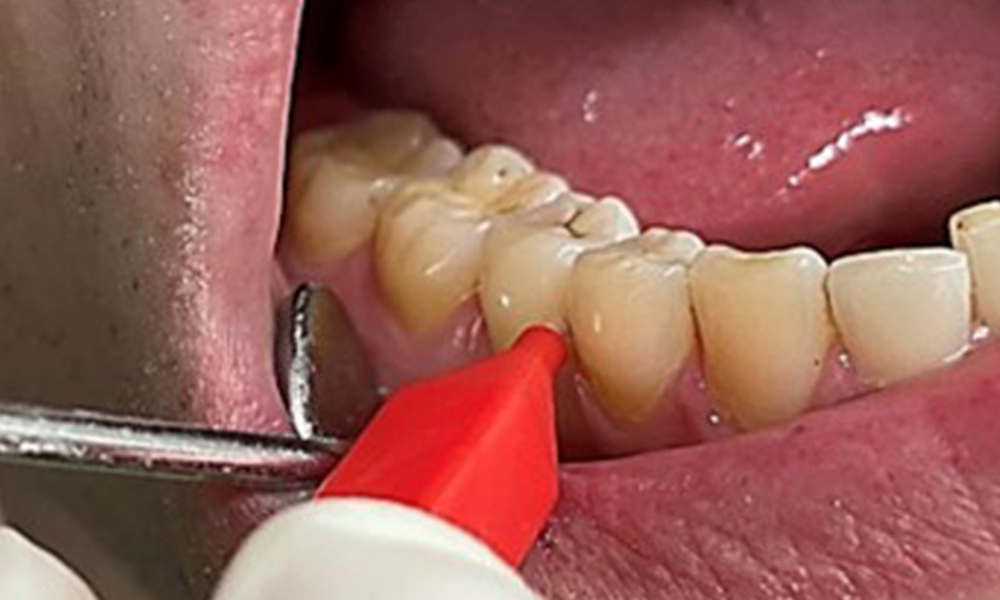

Die Raucher- und Teeverfärbungen lassen sich mittels Pulverstrahl gut entfernen (Abb. 11).

Pulverstrahlanwendung im Bereich der UK Front lingual

Abb. 11 Pulverstrahlanwendung im Bereich der UK Front lingual (hier Proxeo Aura, Firma W&H), © Dr. R. Krapf

Bei Verwendung des höher abrasiven Pulvers ist dringend darauf zu achten von zervikal nach koronal zu arbeiten und die Auslassdüse niemals Richtung Gingiva zeigen zu lassen, um eine mögliche Emphysembildung zu vermeiden. Eine gegenüberliegende gute Absaugung ist unabdingbar zur Reduktion des Aerosols (Abb. 12).

Anwendung des Pulverstrahlgerätes vom Sulkus weg mit gegenüberliegender Absaugung

Abb. 12 Anwendung des Pulverstrahlgerätes vom Sulkus weg mit gegenüberliegender Absaugung, © Dr. R. Krapf